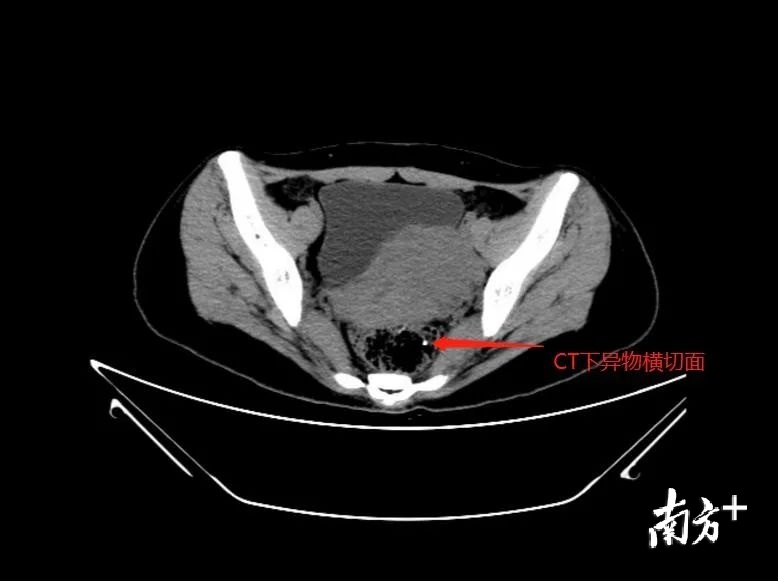

尹医生考虑异物已深入部分肛门内括约肌,而且在不清楚异物的大小及长度的情况下,在门诊直接取出易引起异物断裂、残留,或异物取出后出现肛管出血,止血困难等情况,建议李小姐办理住院在麻醉下手术取出。李小姐住院以后,尹医生马上安排了直肠肛管彩超及盆底CT以进一步明确异物的位置及大小。

根据盆底CT回报考虑异物已穿破直肠壁层。手术中在没有看见异物的情况下,医生凭借B超及CT检查,判定异物垂直插入直肠下段,并穿破直肠壁,进入粘膜下层的位置,最后在切开部分直肠下段粘膜,在距离肛管2厘米处,找到了一米白色异物尾端,并取出。